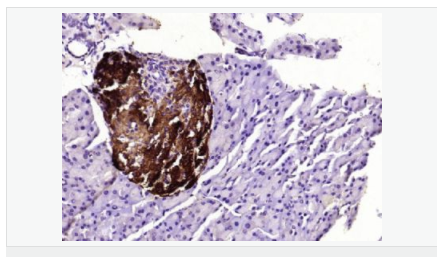

| 產品應用 | WB=1:500-2000 ELISA=1:5000-10000 IHC-P=1:100-500 IHC-F=1:100-500 ICC=1:100-500 IF=1:100-500 (石蠟切片需做抗原修復) not yet tested in other applications. optimal dilutions/concentrations should be determined by the end user. |

| 細胞定位 | 細胞漿 |